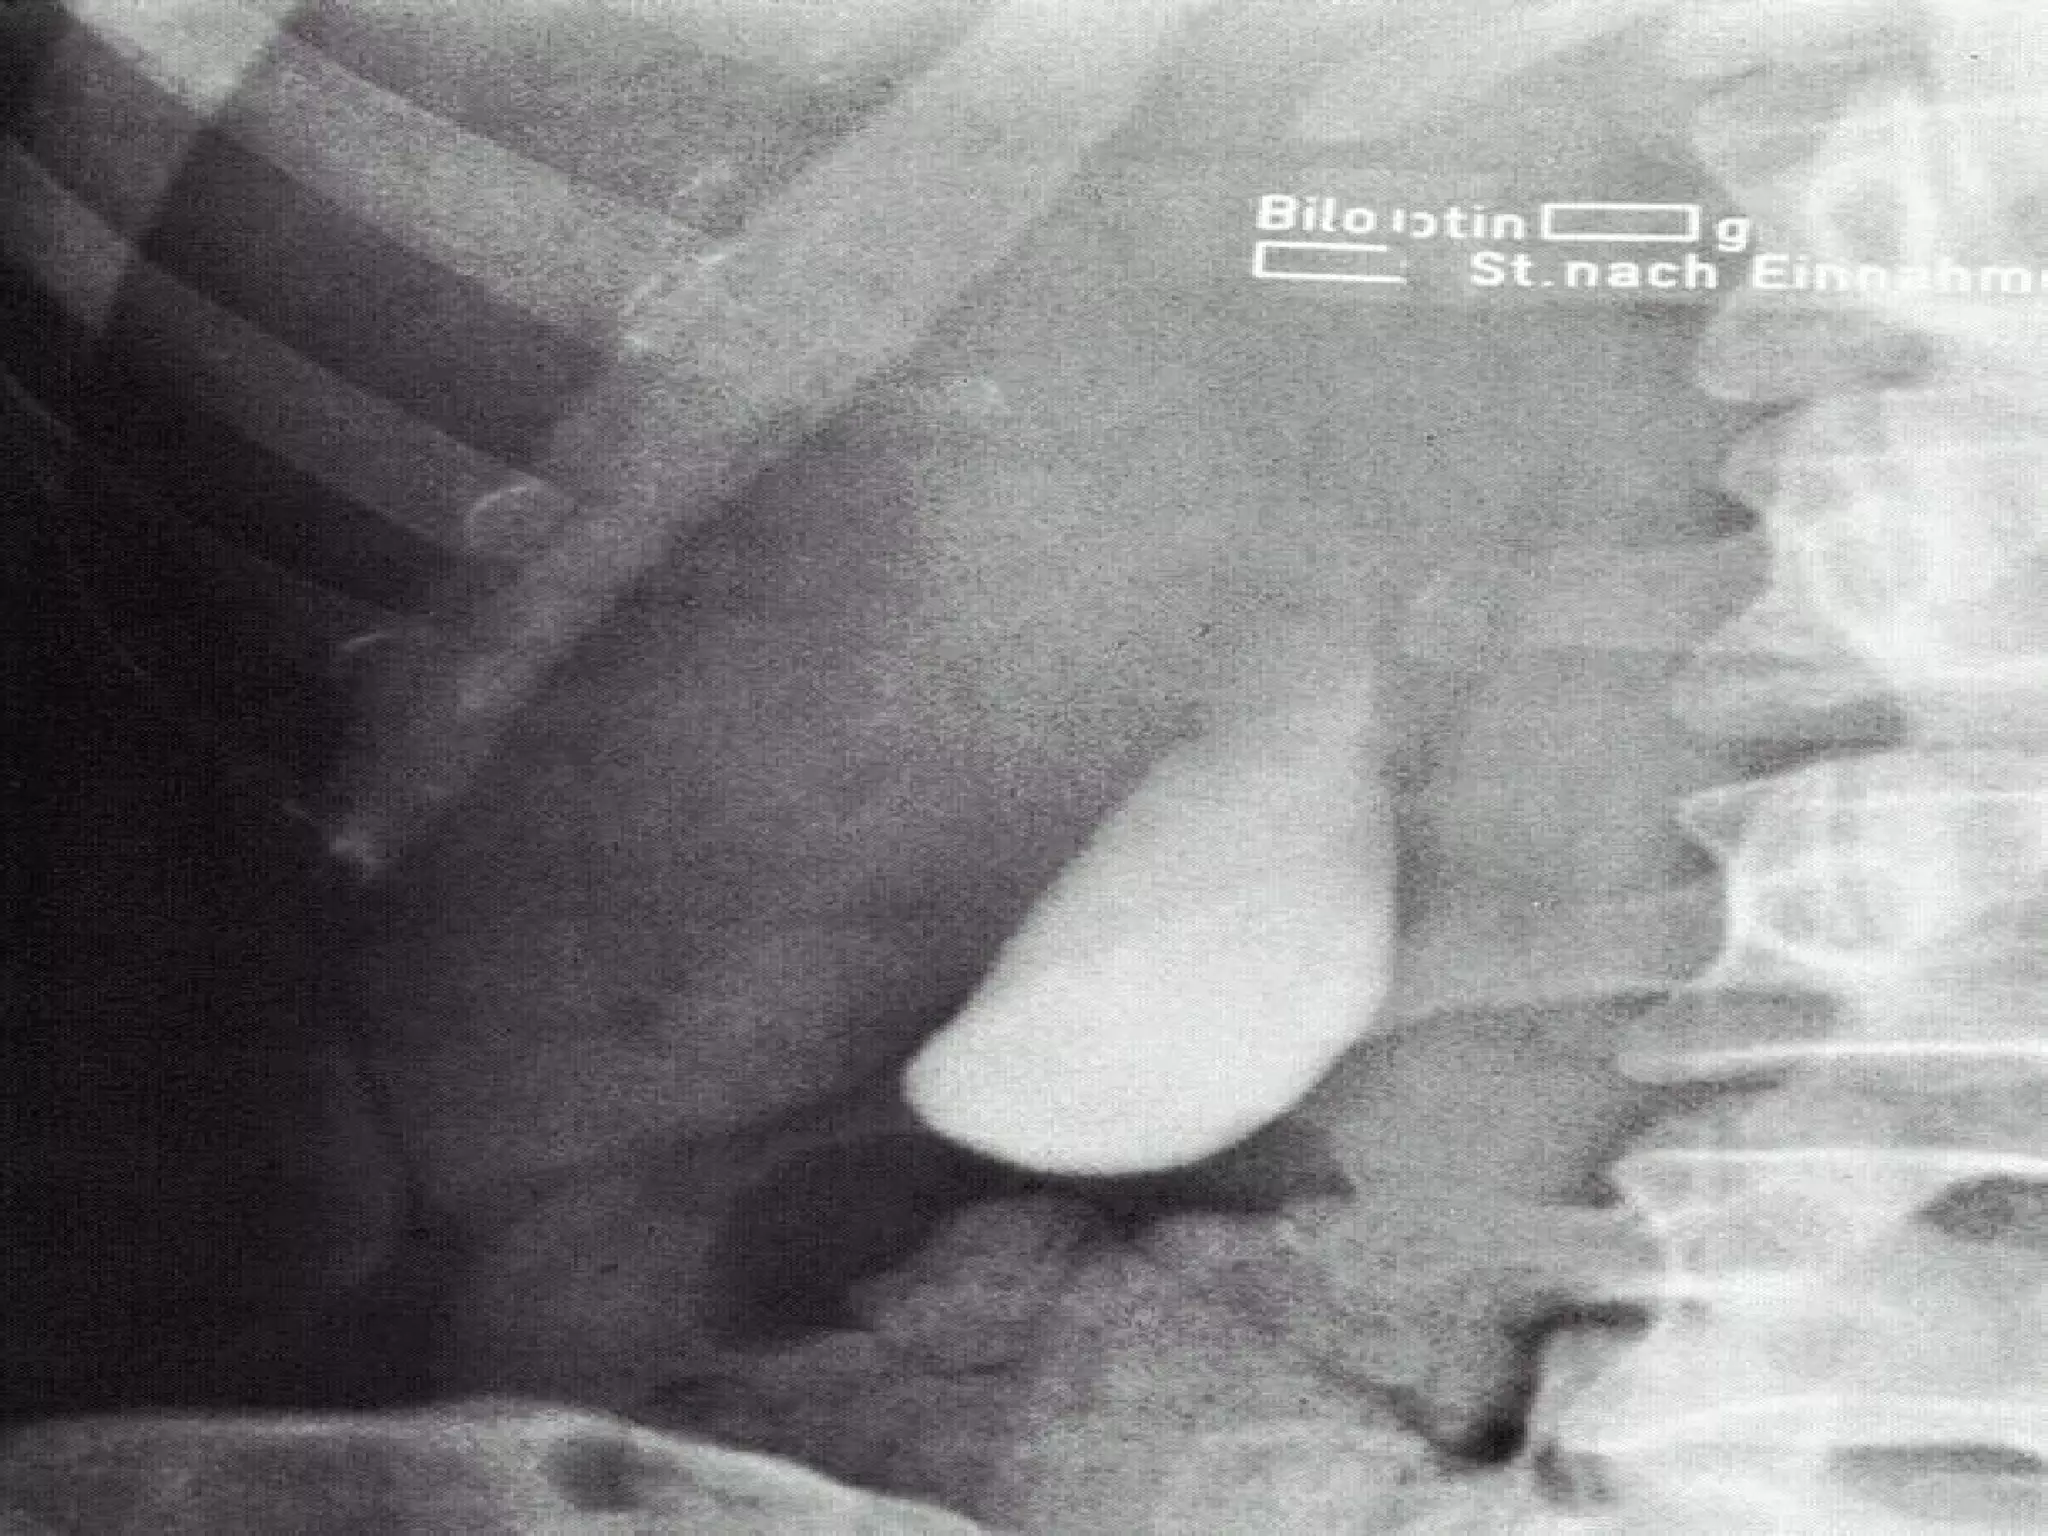

Oral Cholecystogram X-ray visualization of the gallbladder after administration of contrast media Done 10 hours after ingestion of contrast tablets Done to determine the patency of biliary duct

Oral Cholecystogram X-rayvisualization of the gallbladder after administration of contrast media Done 10 hours after ingestion of contrast tablets Done to determine the patency of biliary duct